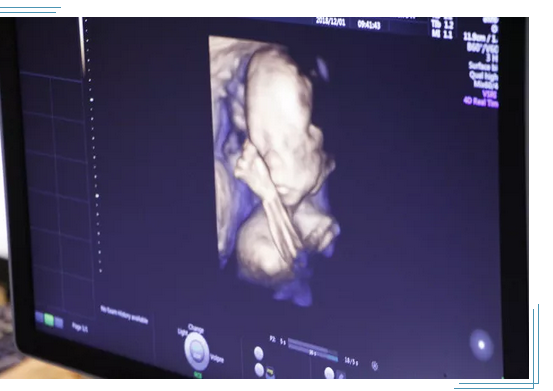

由于在做四维彩超检查的时候,能够实时查看到胎儿的活动,也能给准爸爸妈妈带来乐趣。不过需要注意的是,在怀孕的前12周做四维彩超目前医学界还存在争议,建议孕16 周以后做胎儿四维彩超。

为了每个家庭都能拥有一个健康宝宝,大连美琳达妇儿医院引进新一代GE-E10四维彩超。GE-E10四维彩超能够表面成像,若胎儿有唇腭裂、四肢发育畸形、脑膜膨出、脊柱裂、腹壁裂等先天畸形,都能更清晰地查出来,也有利于医生做出判断。